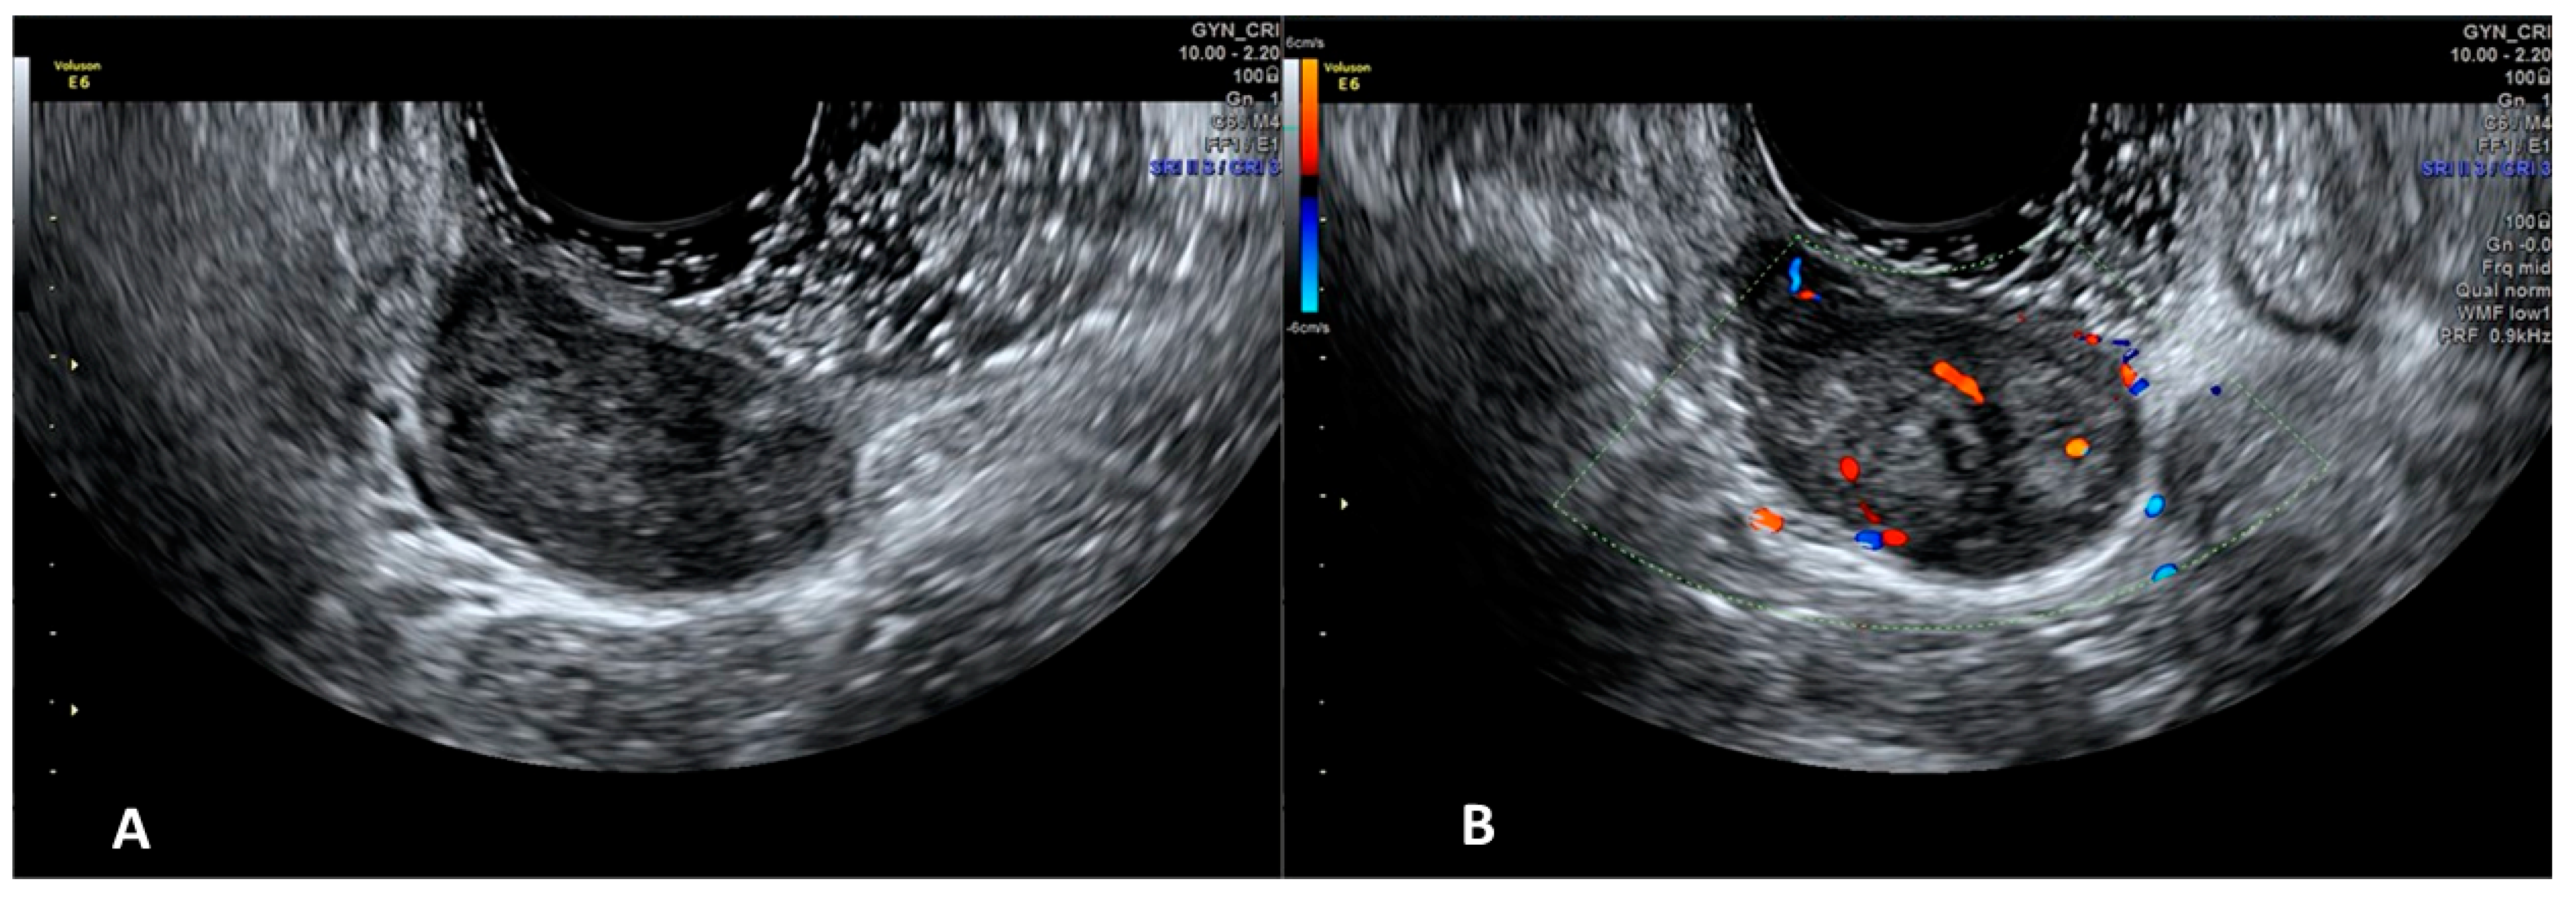

Using conventional sonographic techniques, these masses are inconspicuous and ill-defined, whereas an isoechoic polypoid mass that appears to be jutting directly out of the vaginal wall can be detected using sonovaginography, with the color Doppler to define a central vessel into the polypid mass [17].

Vaginal Leiomyoma

The sonographic appearance of vaginal leiomyomas could easily be mistaken as uterine fibroids. They are usually intramurally situated hypoechoic masses with regular walls and posterior acoustic shadowing and calcifications [16,17]. With sonovaginography, the mass can be more clearly seen within the muscular layer of the vaginal wall (Figure 2). This is essential to being able to differentiate a vaginal wall leiomyoma from the more common prolapse of a submucosal uterine leiomyoma into the vaginal canal [17].

Figure 2. SVG image of a vaginal leiomyoma (Panel (A)) an its vascularization (Panel (B)).